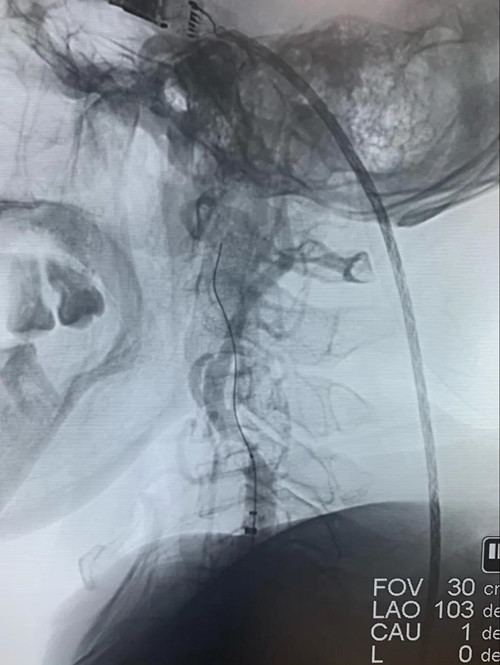

为快速恢复患者颅内脑组织的灌注血流,抽吸导管在球囊辅助下应用“特洛伊木马”技术将抽吸导管快速通过右颈内动脉闭塞病变送至右侧大脑中动脉闭塞处,进行取栓操作。

取栓操作

抽吸导管到右侧大脑中动脉闭塞处进行取栓操作。